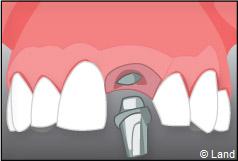

Exemple d’un implant unitaire pour remplacer une dent antérieure manquante.

Un implant dentaire est une racine artificielle, placée par le chirurgien-dentiste dans l’os alvéolaire de l’un des maxillaires en remplacement de la racine d’une dent extraite, qui servira de support à une prothèse. Sa forme est généralement cylindrique ou légèrement conique, ressemblant à une vis, en titane ou en zircone, avec une connexion au niveau supérieur, à l’emplacement de la gencive, pour permettre la pose d’un élément prothétique par vissage ou scellement. Son diamètre varie entre 3 et 5 mm et sa longueur entre 8 et 15 mm. La pose d’un implant, réalisée sous anesthésie locale, est totalement indolore. Elle se pratique au cabinet dentaire ou en clinique.

Pour finir, une prothèse sera mise sur cet implant qui se comportera comme une racine artificielle.